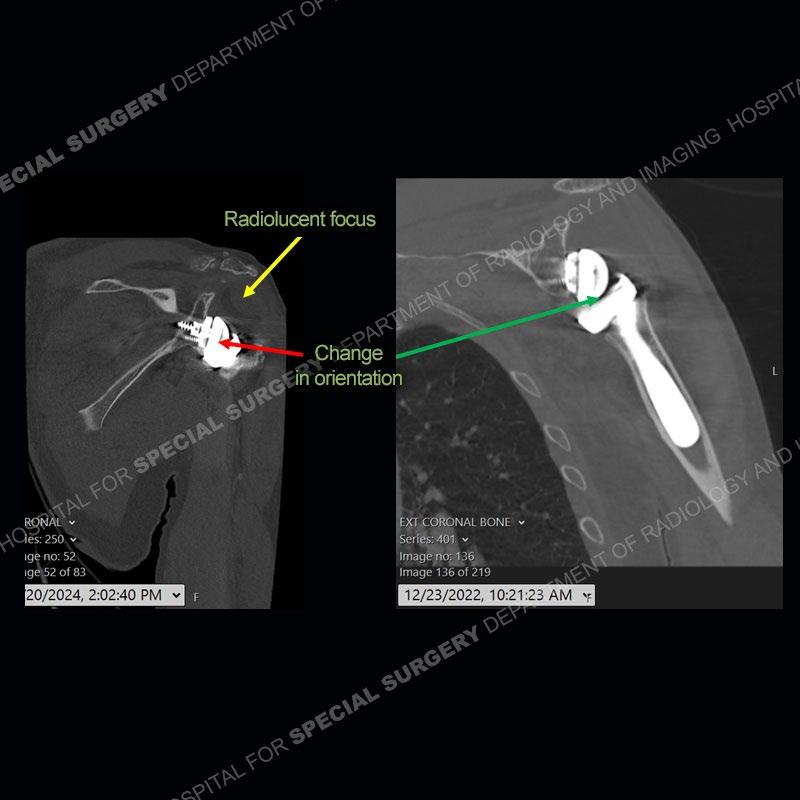

Findings

When comparing the radiographs, there is a slight change in the alignment in the components of the prosthesis. On the current radiographs, a radiolucent, crescentic focus is present at the level of the glenoid. When comparing the CT exams, there is a change at the alignment of the glenosphere and the humeral component and now a direct apposition of the components. On the current CT, the radiolucent, crescentic focus is again identified.

Diagnosis: Polyethylene Liner Dissociation

Total shoulder arthroplasty with a reverse type prosthesis is known to have certain complications such as scapular notching and acromial/scapular spine stress fractures. One of the other unique, but more infrequent complications is dissociation of the polyethylene liner from the humeral tray. Patients will present as in this case with instability and at times frank dislocation. The recognition of this process is important as it is a contraindication to attempt a closed reduction. The closed reduction will typically fail and may damage the components.

If comparison radiographs are present, subtle changes can be made more apparent. Instead of a space between the glenosphere and the humeral tray, there is a direct contact, and there may be an overall change in the alignment at the articulation. The displaced, radiolucent polyethylene liner depending on location can be seen on the radiographs, as in this case. At times, the liner may overlie other structures making identification very difficult on radiographs, but it should almost always be able to be identified on CT (as shown in this example as well). This patient is scheduled for revision procedure.